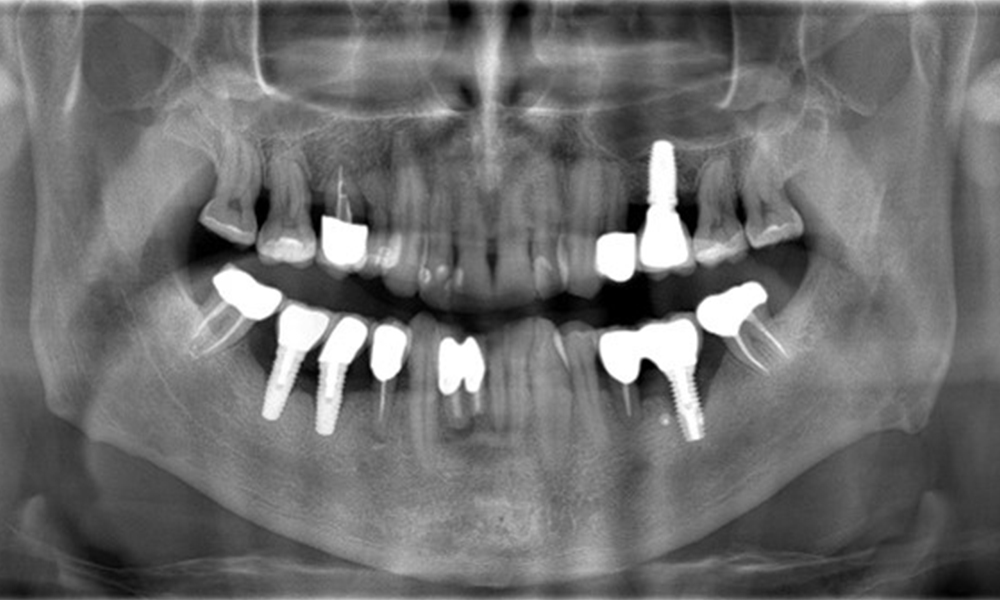

A 52-year-old patient presents at a preventive care session. The patient has no systemic disease and is not taking any medication. He has had various dental treatments and also has two active carious lesions. In addition, the patient has four implants (2nd, 3rd and 4th quadrants). He is revealed to have early periodontal disease (stage IV, grade B). His periodontal condition is stable; a probing depth of Probing depths (ST) of 5 mm is only evident at the implant in region 36. Gingivitis is also identified.

The patient has no particular risk factors with specific dental implications in his medical history. The key factor, therefore, is the requirement in terms of oral health. In this respect, there is evidence of a probing depth of 5 mm at the implant in the 3rd quadrant and, on the X-ray image, increased bone loss. The patient also has currently stable early periodontal disease and two active initial carious lesions.

Because of the history of periodontal disease and peri-implantitis, check-ups initially every three to four months following successful treatment for peri-implantitis are recommended.